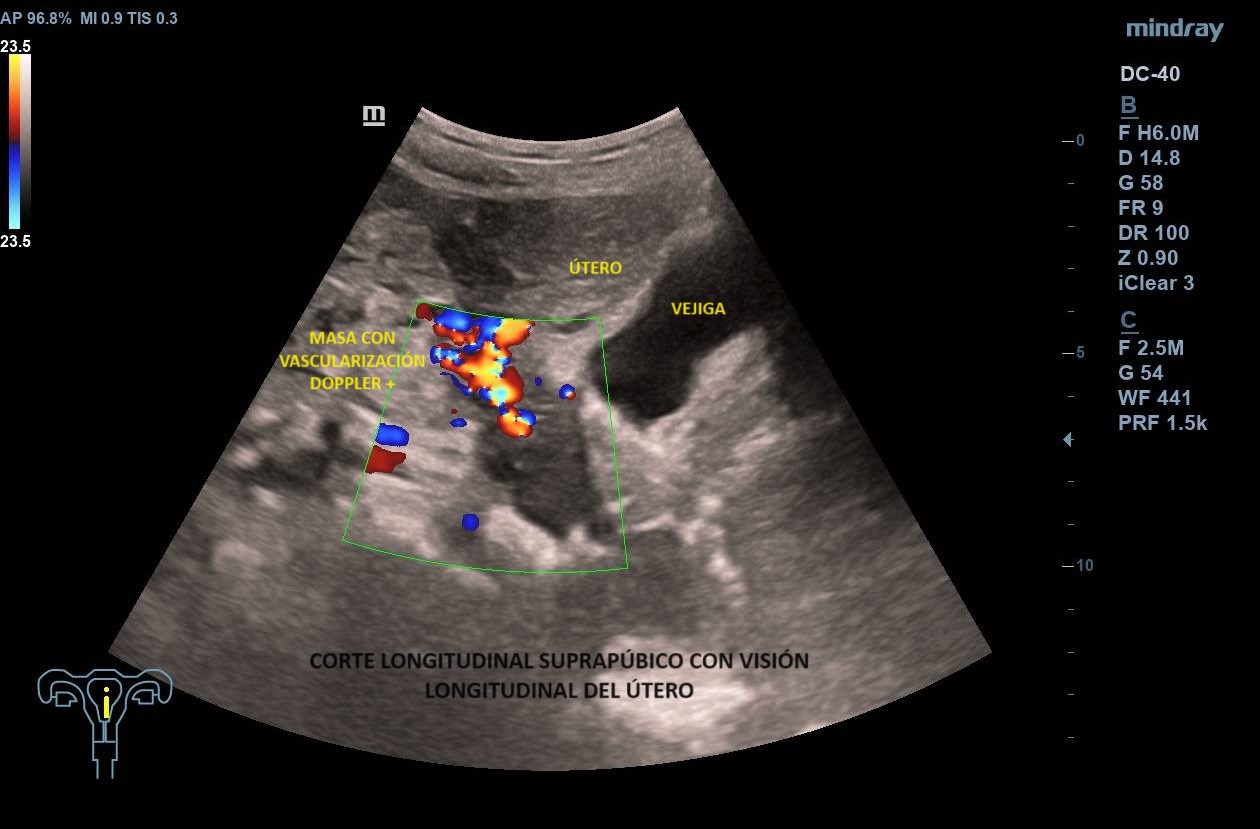

Ecografía abdominal clínica: Masa heterogénea que ocupa todo el abdomen, de aspecto sólido, vascularizada con zonas hipoecoicas-anecoicas en su interior. Riñones con eco-estructura sin alteraciones, hígado sin LOES. Vejiga sin engrosamiento de paredes, útero parcialmente visible. Anejos y retroperitoneo no valorables. No líquido libre.

Los leiomiomas uterinos son el tumor más frecuente de pelvis en la mujer. La ecografía es la primera línea de estudio. Habitualmente s

e describen como masas bien delimitadas redondeadas hipoecoicas con sombra acústica, aunque también pueden tener áreas isoecoicas e hiperecoicas. Pueden presentar necrosis central (áreas anecoicas) o calcificaciones, sin implicar malignización. El Doppler-color suele mostrar una distribución irregular de los vasos. El diagnóstico definitivo es el anatomo-patológico.